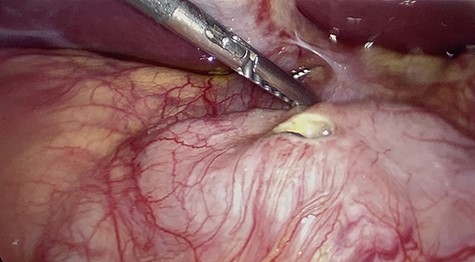

All of the standard preoperative measures were taken and the patient was prepped and draped for laparoscopic cholecystectomy. Ports were placed in a typical fashion for this operation, with A 12 mm Hasson trocar placed in a supraumbilical position, and 5 mm trocars placed in the epigastrium and RUQ x2. Upon insertion of the laparoscope, the uterus was still large in the pelvis and there was a small amount of bloody fluid in the abdomen. The fundus of the gallbladder was grasped and retracted cephalad. With this maneuver it appeared that the duodenum had fused itself to the infundibulum of the gallbladder. Upon gently peeling the duodenum off of the gallbladder, it became obvious that there was a perforated duodenal in the first portion of the anterior duodenum and had been the gallbladder that sealed the perforation (Figs 4–6). The gallbladder showed signs of erosion at the site where it patched the duodenum as well (Fig. 6). At this time we proceeded with laparoscopic cholecystectomy first, prior to addressing the duodenum. Once successfully completed with the cholecystectomy, we performed a laparoscopic graham patch with our existing ports, which can be seen in Fig. 7. A #10 flat JP was inserted in the region of the graham patch. The abdomen was irrigated and then suctioned clean. The repair was confirmed by placing underwater with the second portion of the duodenum compressed, while anesthesia insufflated the stomach/duodenum through an OG tube. The patient tolerated the operation well, extubated, and transported to recovery.

The gallbladder had been gently resected from the duodenum revealing a nonperforated ulceration where it had been patching the duodenal ulcer.